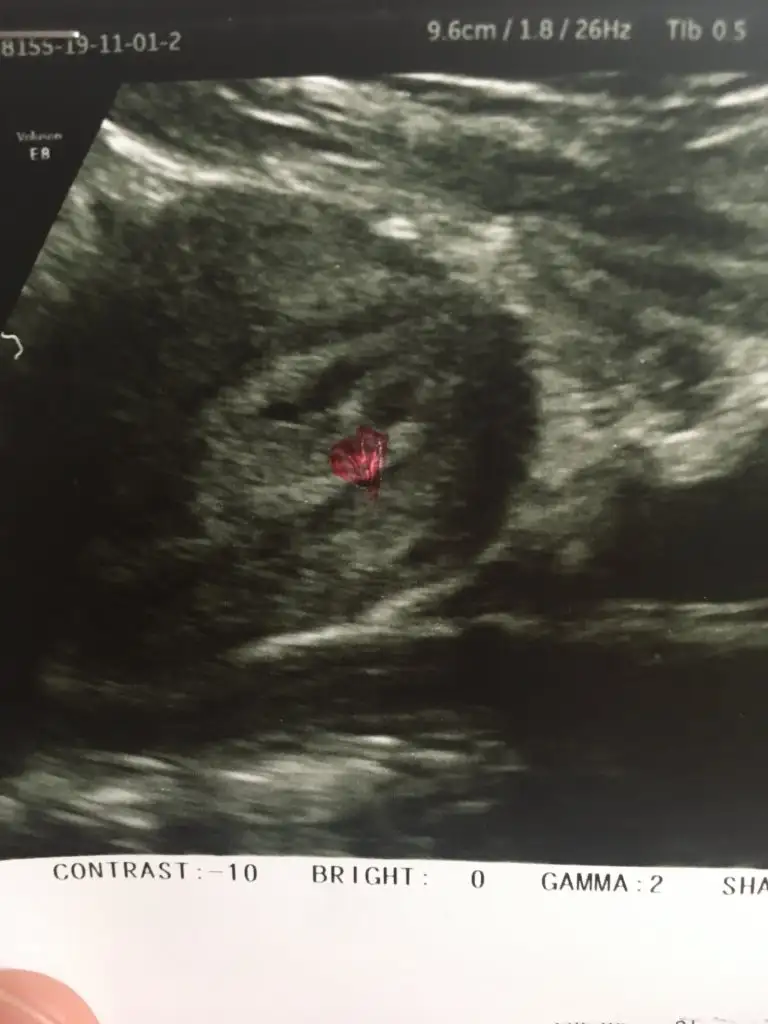

Ay Allah razı olsun bazısı ultrasonda kanama alanı görünüyor dedi fotoyu gösterince ama doktor yok dedi dün bana düşük riskin bak ultrasonumBenimde kese göründükten 5 gün sonra 6. Haftada ve 7.haftada iki kez kanamam olmuştı hemde seninki gibi değil çok yoğun adet kanaması gibi ve kese yanında yoğun kanama alanı çıkmıştı şimdi 12.haftadayım hiç bir problemim kalmadı çok şükür.. senin kanama alanın bile yokmuş ve gelen kan azmış o yüzden merak etme geçecektir bu konuyu çok araştırdım bazı kişilerde olabiliyormuş kanama ve bebekte kromozal bir bozukluk yoksa %80 bebek sağlıkla doğuyormuş o yüzden içini ferah tutmaya çalış canım ve sen yinede tedbirini al ağır iş yapma bol bol dinlen ilk 3 ay Rabbim sağlık versin ikinizede

Fotoğraftan anlaşılması zor canım ama doktorun yok dediyse öyledir riske atmaz heralde ama içim rahat olsun diyosan başka bir doktorada gidebilirsin ben 3 doktora gitmiştimAy Allah razı olsun bazısı ultrasonda kanama alanı görünüyor dedi fotoyu gösterince ama doktor yok dedi dün bana düşük riskin bak ultrasonum

Vajinal ultrasyona baktiysa ondandır benimde aynısı olmuştu kontrolden sonra bi kaç gün geldi açık kahverengi şeklinde sonra kesildiMerhaba arkadaşlar normalde 6 haftalık gebeyim ama geç döllenme olduğu için 2 hafta geriden geliyormuş doktorum dün keseyi gördü ve kanama alanı yok dedi şayet bu haftalar kanama lekelenme görebilirsin telaş yapma dedi doktor kontrolünden geldikten 2 saat sonra idrarımdan sonra kahve lekeler ve kırmızımsı kan geldi doktoruma mesaj attım yerleşme dedi progestan kullanmaya başladım dün akşam hala idrardan sonra kanama var böyle bişey yaşayanlar varsa bana bilgi verebilirmi sanırım fazla evham yapıyorum ama kanı her gördükçe içim sıkılıyo